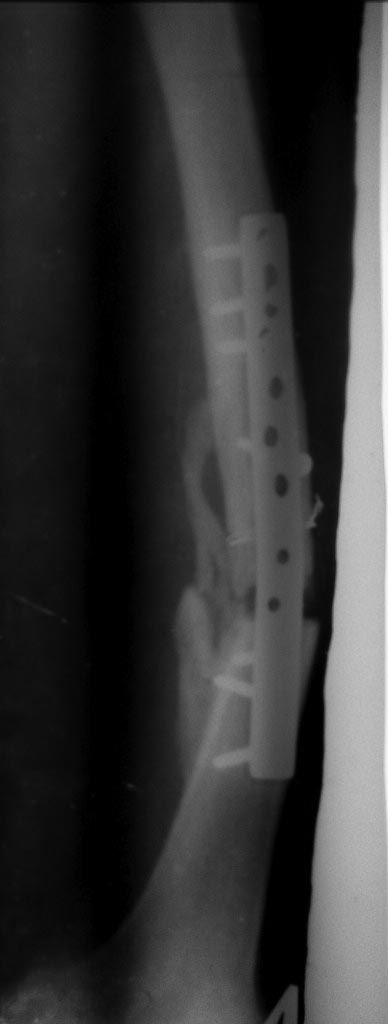

Доброго времени суток! Лечение нереактивного псевдоартроза: адаптация концов отломков, костная пластика и стабильная фиксация. По состоянию костей на настоящее время требуется блокируемая пластина. В дальнейшем приступите к разработке коленного сустава. Никакой аппарат Вам не даст в полной мере разработку сустава по понятным причинам. Большое спасибо!

Ничего подобного не замечал особенно на голени.С аппаратом Илизарова мы пережили тяжелое время- девяностые когда кроме спиц ничего не было,заместили кучу дефектов на фоне остеомиелита и все срасталось и не было контрактур особенно в коленном суставе.Нужно просто не нарушать методику проведения спиц.Этот перелом требует не трансплантации ,а адекватной репозиции и жесткой фиксации и не повредила бы ранняя нагрузка на конечность.Посмотрите на снимок-дистальный отломок как будто протянул маленькую ручку к проксимальному-вроде как просит- приблизь его и мы сольемся воедино!

С вами согласен полностью, сколько мы прооперировали пациентов в 90-х!!!!! Всё срасталось на ура! Тут нужен внеочаговый остеосинтез , каким аппаратом? - это выбор мастера - репозиция + остеотомия м/берцовой кости!

От ЧКДО больной котегорически отказывается, я тоже полагаю, что лучше ставить блокируемую пластину.

Согласен с Андереем Кияночкиным. Вопрос давно решенный: с биологией голени все в порядке, потенциал к сращению не утерян . После этапной постепенной коррекции деформации любой метод СТАБИЛИЗАЦИИ перелома приемлем и функционален: БИОС,АВФ,LCP,DCP.